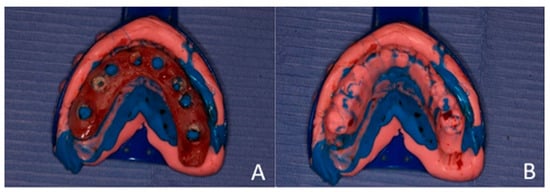

The dentures were modified by enlarging the pre-existing guide holes to facilitate complete seating on the alveolar ridges. The flanges of the lower denture and the palatal portion of the upper implant-supported dentures were excised to expose the hard palate and the lingual aspect of the lower ridge, thereby providing a reference surface for the subsequent impression.

Plastic caps were placed on the abutments of the implants, and Teflon tape was packed into the open incision lines and extraction sockets to prevent the injectable crown bridge material from entering and solidifying within them, as this could compromise the surgical success of the implants (Figure 7).

Figure 7. Teflon tape is used to cover the incision wounds. Plastic caps are shown. (A) Maxillary arch. (B) Mandibular arch.